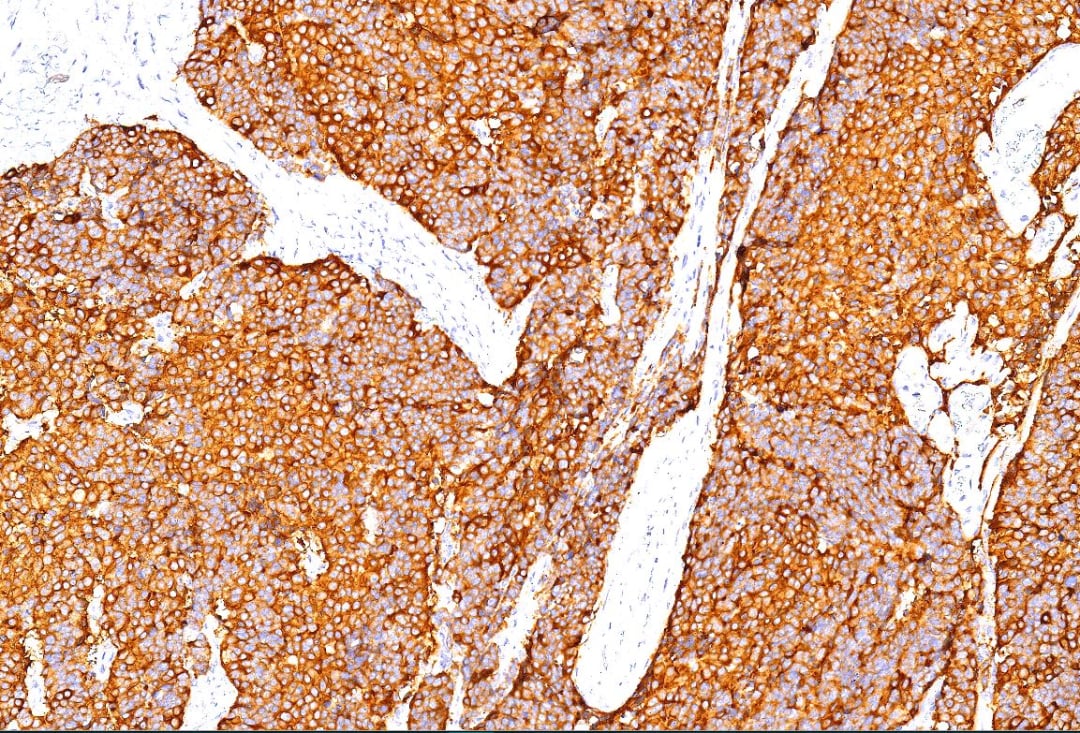

免疫组化染色可以进一步确认肿瘤的神经内分泌来源。在本病例中,肿瘤细胞表达多种神经内分泌标志物,如 Syn(突触素)、INSM1、CD56 和 CgA(嗜铬粒蛋白A)。同时,p16 蛋白的强阳性表达,也印证了其与高危型HPV感染的相关性。值得注意的是,Ki-67增殖指数高达80%,这表明肿瘤细胞正在快速、不受控制地分裂,是其高度恶性的又一佐证。

肿瘤细胞Syn阳性。